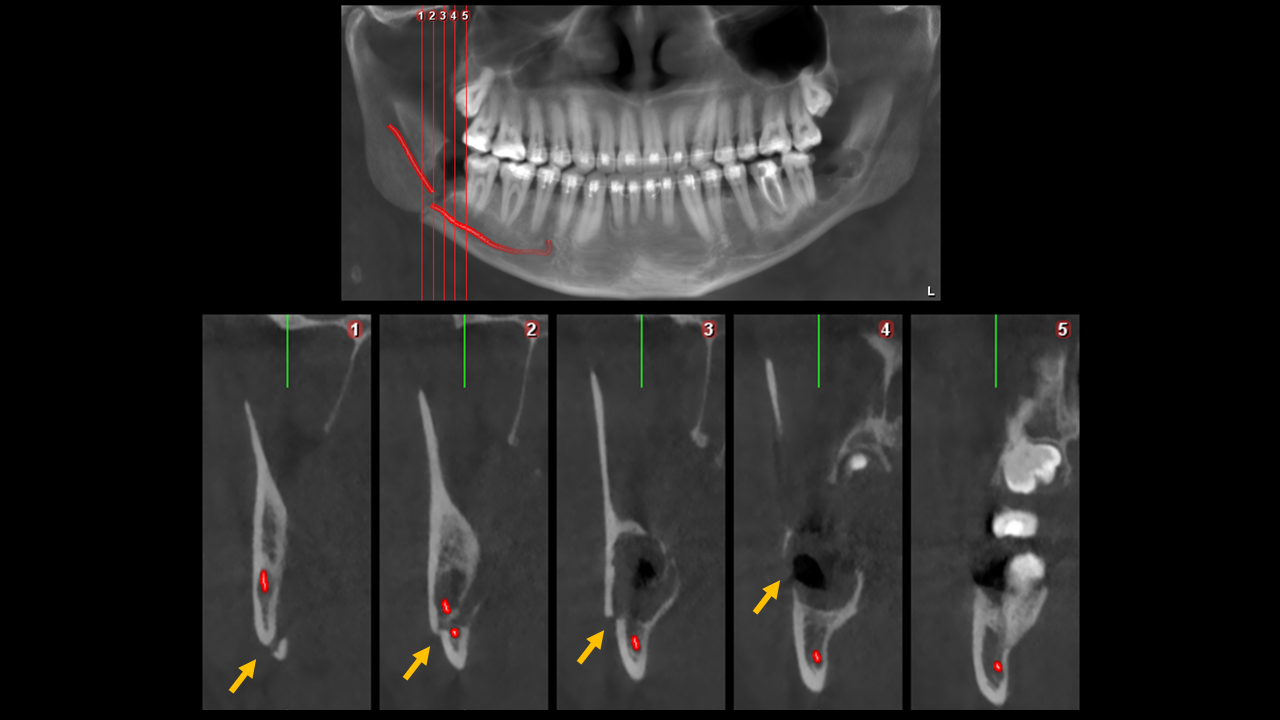

Figura 5: Vistas Transaxiales

En las vistas transaxiales (Figura 5) vemos la fractura con dirección hacia abajo y hacia atrás, encontramos que el segmento posterior tiene un desplazamiento lateral y el segmento anterior presenta un desplazamiento hacia caudal.